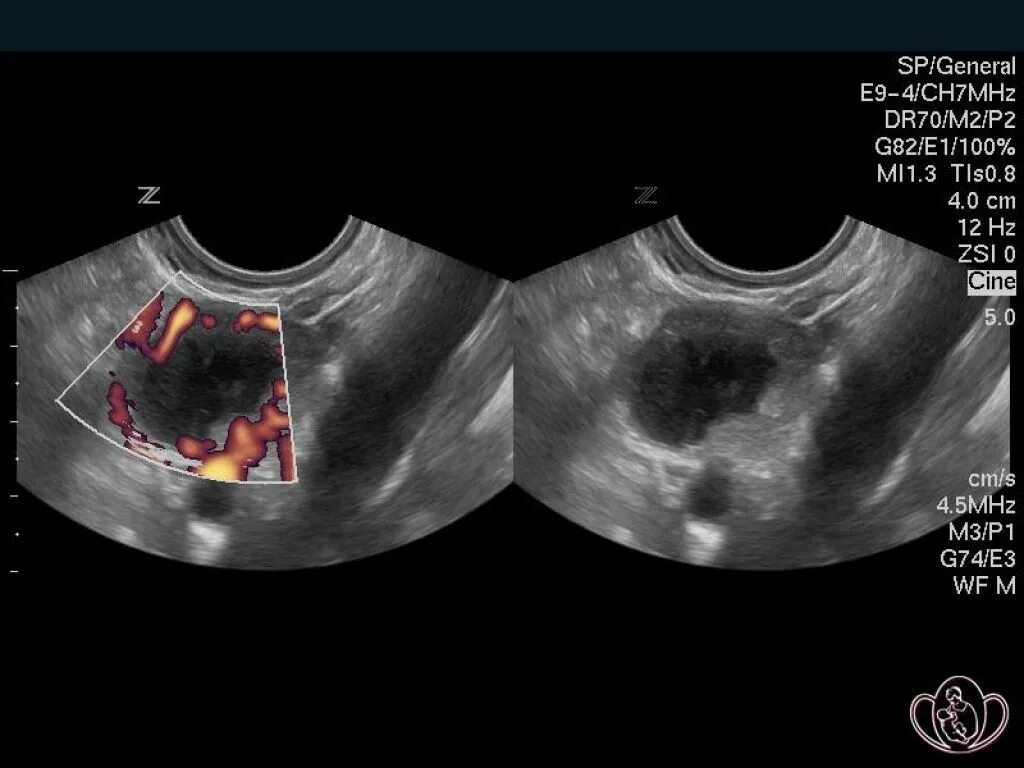

Как выглядит яичник